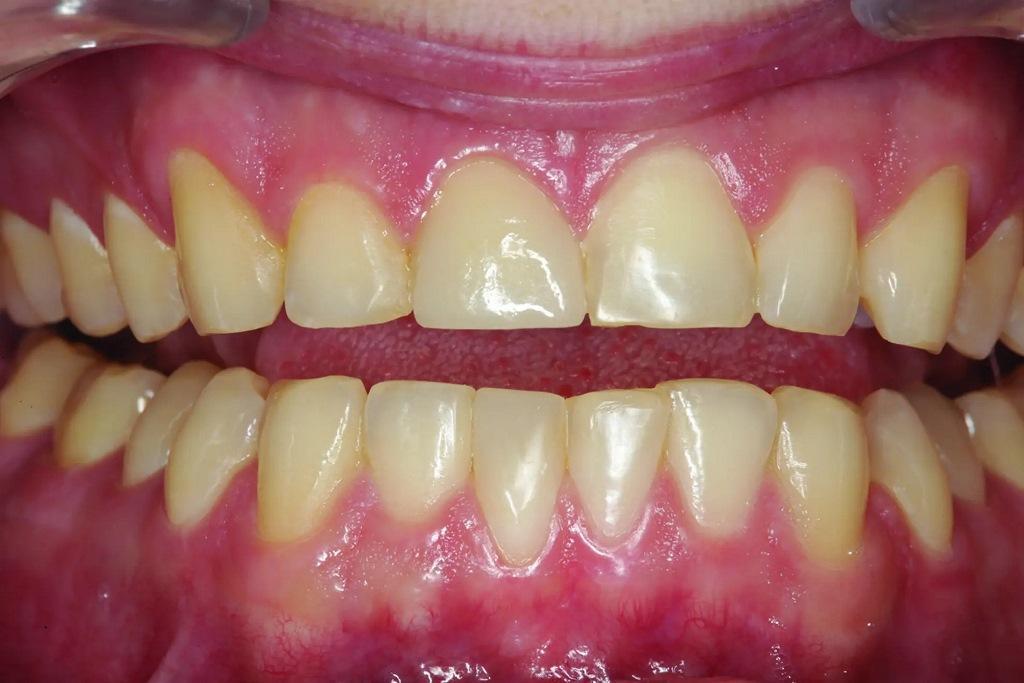

Пациент обратился со сколом композитной реставрации IV класса на зубе 11 по причине дефекта (фото 1). За последний год проводили реставрацию трижды и она снова скалывалась. Было ли это из-за плохой техники или по причине некачественных материалов? Более чем вероятно, что это произошло из-за окклюзии. Помимо большого количества композита на лицевой поверхности, который выходил за пределы области скола, большая часть небной поверхности зуба была стерта до дентина из-за гиперфункции при протрузии и боковом перемещении в течение многих лет, что создавало для пациента функциональную и эстетическую дилемму. «Консервативный» подход, возможно, заключался в том, чтобы снова заклеить зуб композитом и надеяться на лучшее. Однако, возможно, это был не самый лучший долгосрочный подход, учитывая функциональную нагрузку в этой области, даже при наилучшем выравнивании зубов. В конце концов, насколько консервативно постоянное воздействие на зуб вращающимися инструментами для фиксации композита, который продолжает разрушаться?

Фото 1: Предоперационный снимок лицевой стороны реставрации из композитного материала со сколом на зубе 11 в максимально сжатом положении.